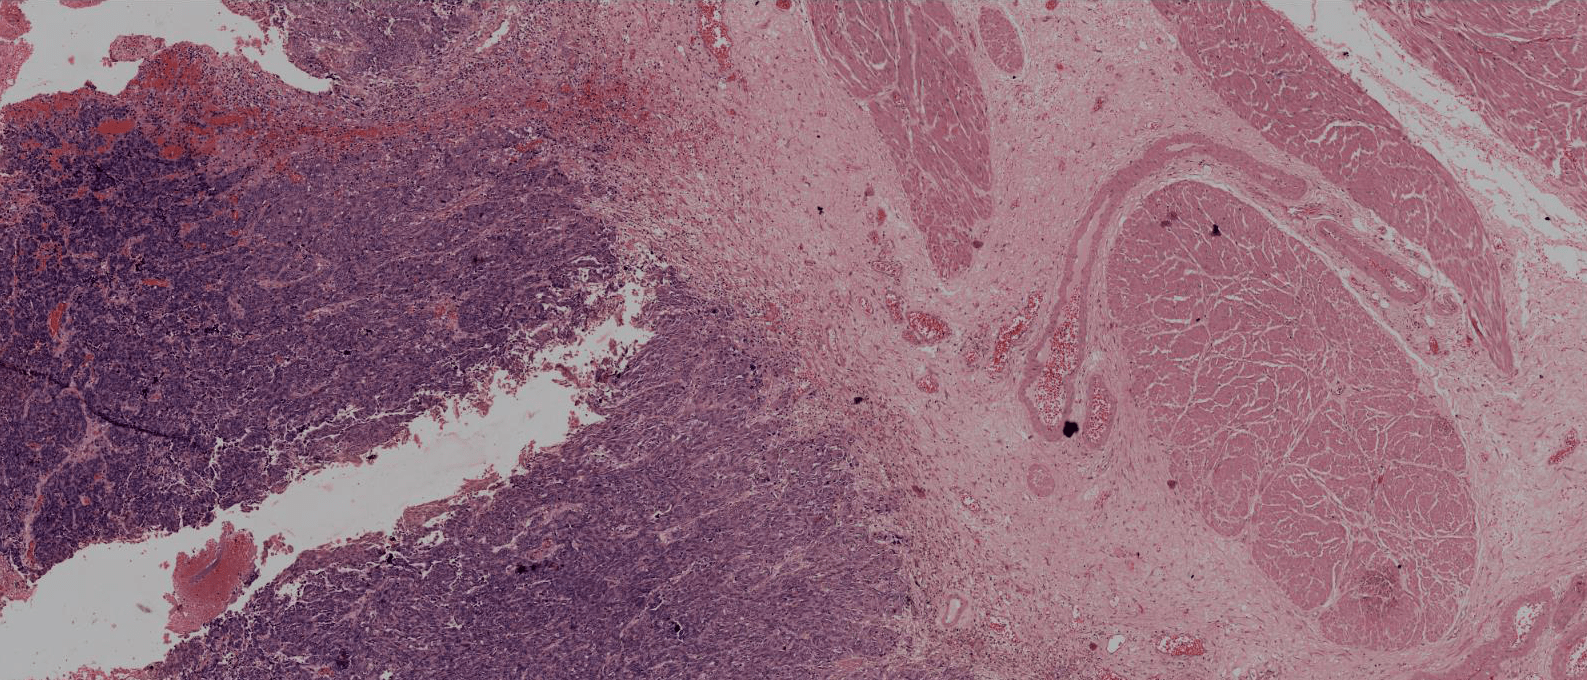

In this report we describe the case of a renal allograft recipient who presented with graft dysfunction and was diagnosed to have BK virus associated nephropathy 9 months post renal transplant. He developed progressive graft dysfunction despite reduction of immunosuppression. Forty six months post transplant he presented with gross hematuria and was diagnosed on cystoscopy guided biopsy to have an urothelial cancer of the urinary bladder. The histopathology showed high grade invasive urothelial carcinoma with focal squamous differentiation.